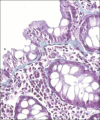

Figure 1

A case of lymphocytic colitis showing marked increase of lymphocytes within the lamina. H and E stain, ×100